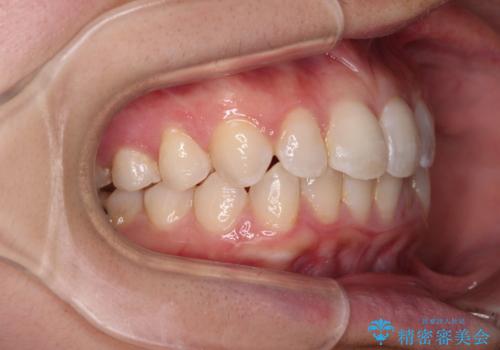

- 前歯のデコボコと歯肉に埋もれている奥歯を気にして来院された患者様です。

インビザラインでの治療を希望されていましたが、左右の下顎大臼歯が歯肉に埋もれており、特に右側は歯軸が顕著に傾斜していたため、インビザライン単独での治療は困難と判断し、ワイヤー装置を併用することとしました。

ワイヤー装置での下顎臼歯改善には時間がかかることが予想されたため、下顎のワイヤー矯正と並行して上顎をインビザラインで整え、その後インビザラインにより上下歯列を整える矯正治療を行うこととしました。

ワイヤー装置を併用したことで、レントゲン写真からも分かるとおり歯軸をしっかりと改善させることができました。